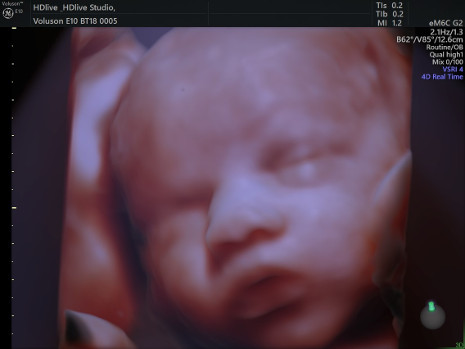

, cuenta con un ecógrafo de última generación Voluson E10 BT18, capaz de ofrecer imágenes de alta definición en 2D, 3D y 4D HD live Silhouette- HD liv estudio desde las primeras semanas de gestación y una excelente penetración para exámenes técnicamente difíciles tanto fetales como ginecológicos.

"Además, es importante destacar el factor emocional. Para las futuras madres ver la cara de sus hijos de forma tan definida consigue aumentar el vínculo madre-hijo desde mucho antes del nacimiento".